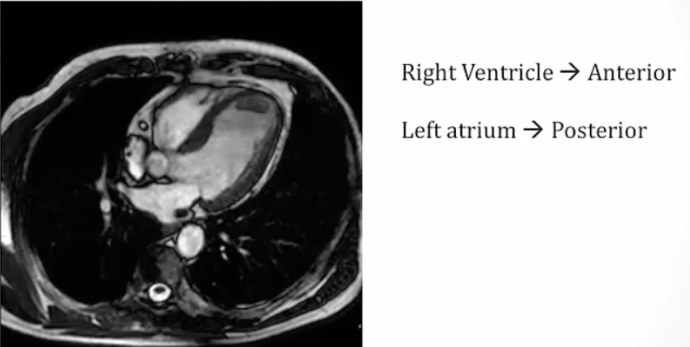

Left Atrium

[_](Left atrium location and why it's important)The most posterior chamber of the heart. Anterior to the esophagus. Thus, enlargement can cause:

Dysphagia by compressing the esophagus

Hoarseness by compressing the left recurrent laryngeal nerve.,

Esophagus: black hole between aorta and left atrium